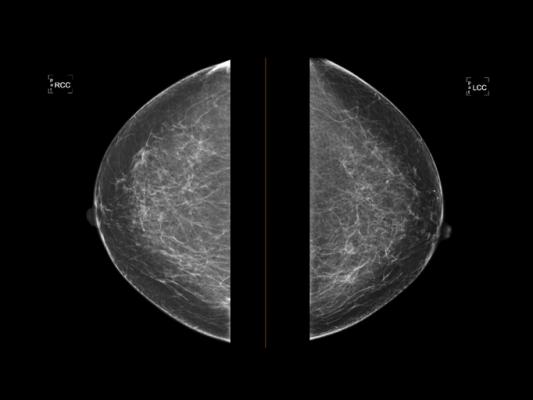

“Higher density breast tissue on mammograms means higher risk for breast cancer,” says Dr. Susan Holley, clinical director of Onsite Women’s Health and presenter of the abstract. “Therefore, breast density is an important variable to get right. We wanted to know if an AI tool could help us be right more often, over the long-term.”